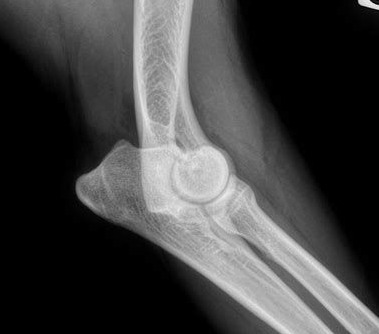

Dépistage de la dysplasie de coudes

Dysplasie du coude

Explications et point sur les denieres avancées en connaissances des origines, mécanismes, et traitements de la pathologie. Article du Dr Jean-Marc Wurtz, 2021.